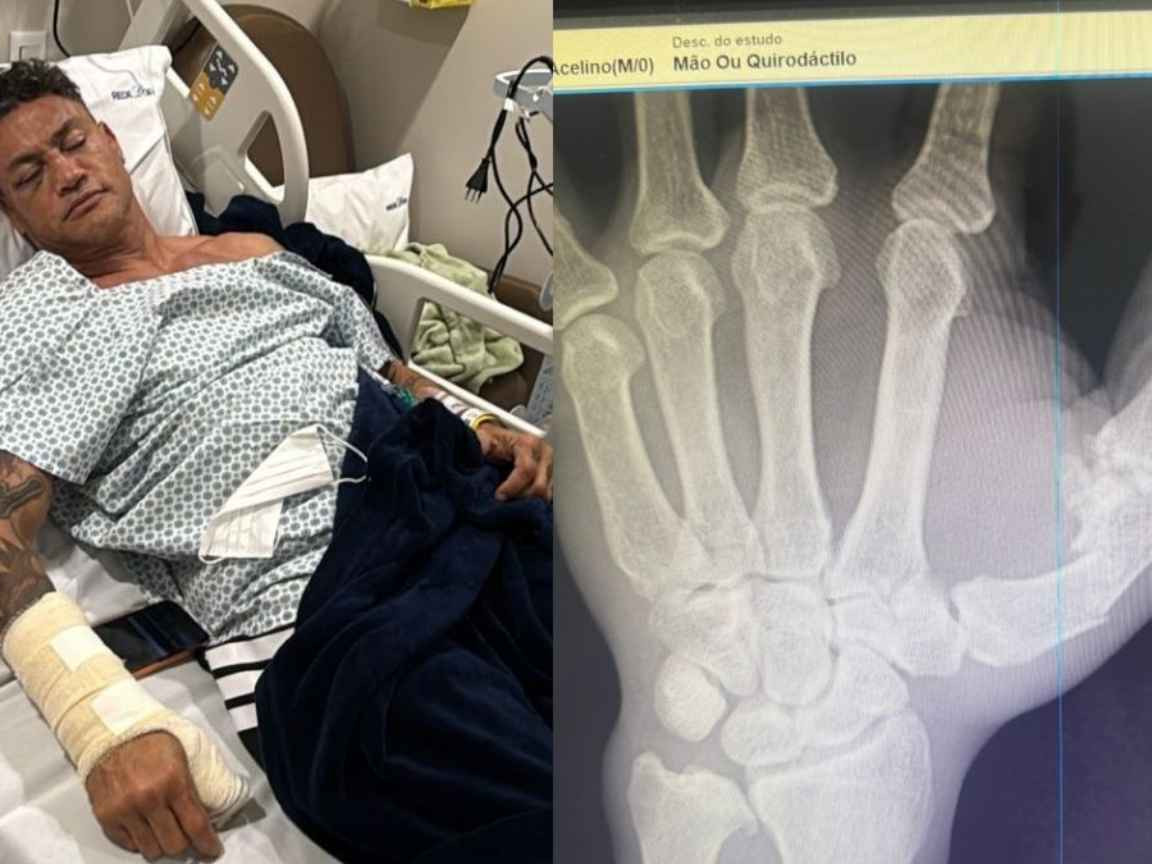

Do leito do hospital, Popó quebrou o silêncio, rebateu as acusações de que teria premeditado a confusão e atribuiu a “selvageria” à equipe adversária. Sua assessoria confirmou que o procedimento cirúrgico é para corrigir uma fratura no polegar direito.

A assessoria do atleta explicou à imprensa que a cirurgia será necessária por causa de uma fratura no polegar direito, sofrida durante a confusão no ringue. Além da operação na mão, Popó também passará por uma bateria de exames para verificar se sofreu alguma lesão na cabeça, em decorrência de supostas cabeçadas que teria recebido de Wanderlei Silva durante o combate, antes da desclassificação.